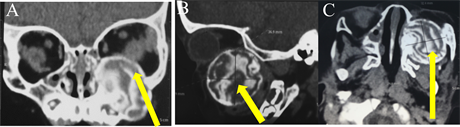

CT Scans revealed a well-circumscribed heterogenous lesion in the left maxillary sinus, with displacement of the orbital floor (Figure 2).

Figure 2. CT scans revealed well-circumscribed, heterogenous lesion (yellow arrows) in the left maxillary sinus, with superior displacement of orbital floor ((A) coronal section; (B) sagittal section; (C) axial section).